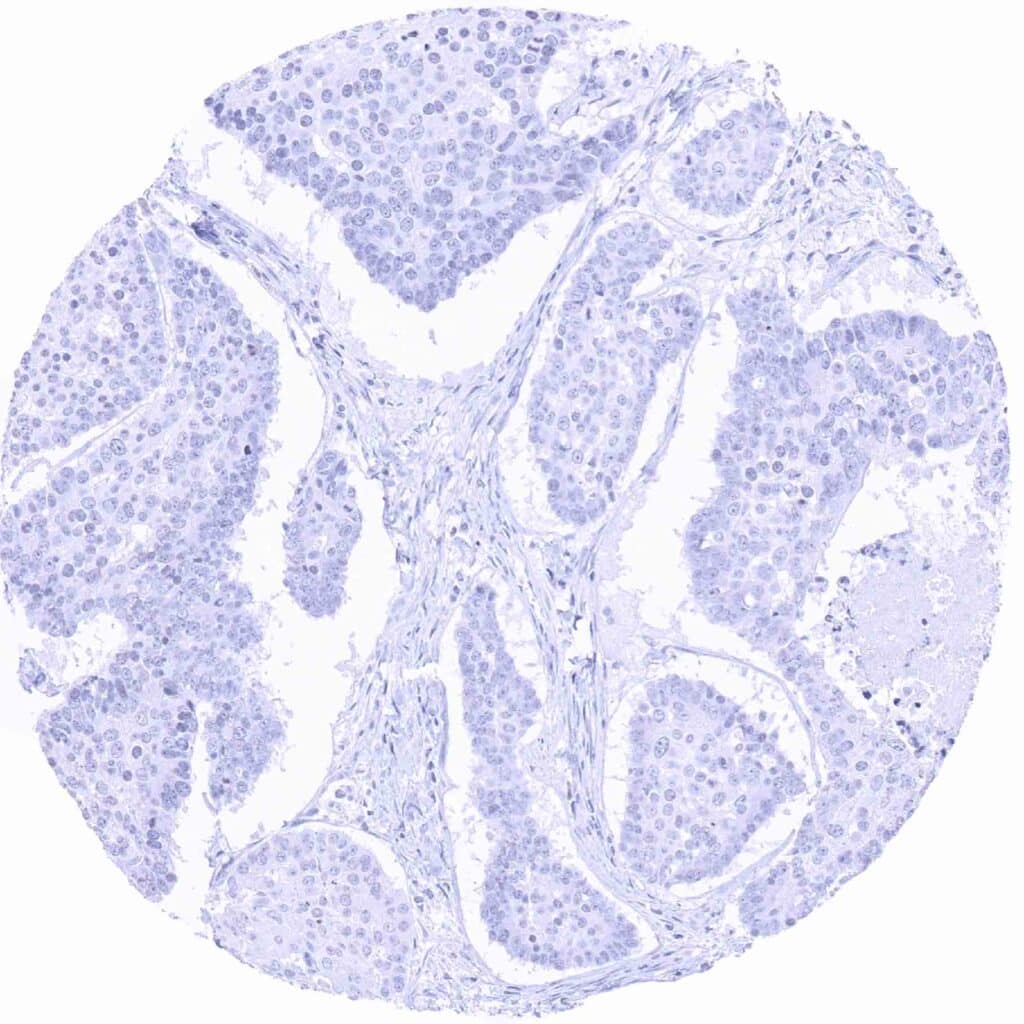

Prostate – Adenocarcinoma (Gleason 3+3=6) with strong Prostein immunostaining of tumor cells